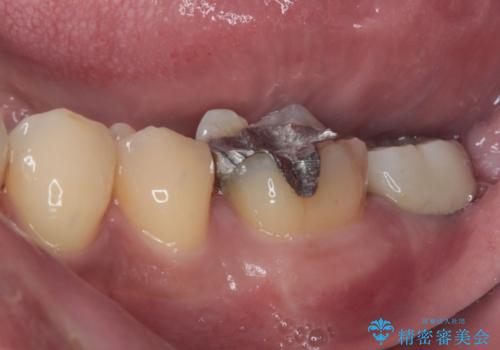

- 左下の歯が欠けてしまったとのことで来院された患者様です。

大きな銀歯が装着されており、その周りからむし歯が広がっている状態でした。

特に症状はなく、神経組織も健全な状態であったため、むし歯を全て取り切った後にフルジルコニアクラウンにて補綴することとしました。